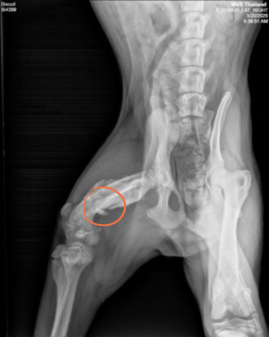

Our team brought Biscuit to the brand new WVS clinic in a city called Chiang Mai. First stop? A check-up with the vet and a set of x-rays. That’s how we discovered that Biscuit had a fractured leg. The bone had already started healing, but not quite right; one of his legs was now a different length to the others!